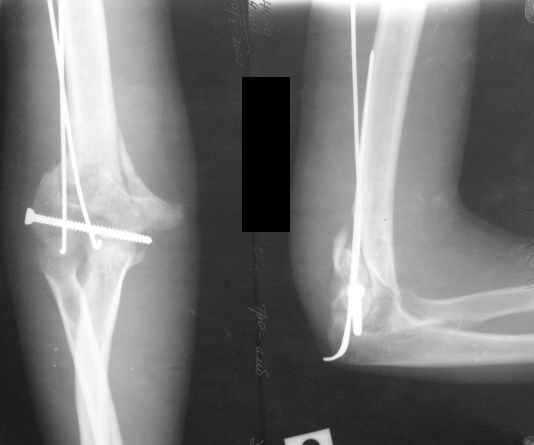

The recent x rays show established Non union with poor quality bone in the distal fragement. The joint is also appearing degenerate. In view of the multiple failed reconstructive surgeries, an Elbow replacement would seem reasonable.

However it would have to be a fully constrained one as there would be missing bone stock.